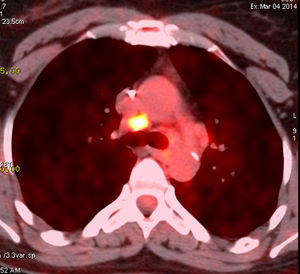

La paciente fue sometida a radioterapia postoperatoria (45Gy) y tratamiento hormonal (tamoxifeno) durante 12 meses. Dos años más tarde, se observaron algunas metástasis nuevas en los ganglios linfáticos axilares del lado derecho que fueron extirpados. Un año más tarde, un TAC torácico mostró múltiples ganglios linfáticos en el mediastino con captación positiva de FDG en el PET (fig. 1). La broncoscopia fue normal. Dado que el valor de SUV fue bajo, se repitió el estudio de FDG-PET 3 meses más tarde, que mostró un crecimiento estable de los ganglios linfáticos. Se realizó una biopsia de los ganglios linfáticos mediante mediastinoscopia que reveló un granuloma con células gigantes sin caseum compatible con sarcoidosis. La paciente fue tratada con corticoides con buen resultado.

| PET/CT torácico: ganglios mediastínicos | SUVmax a 3,6 | SUVmax a 5,1 | SUVmax a 8,7 |